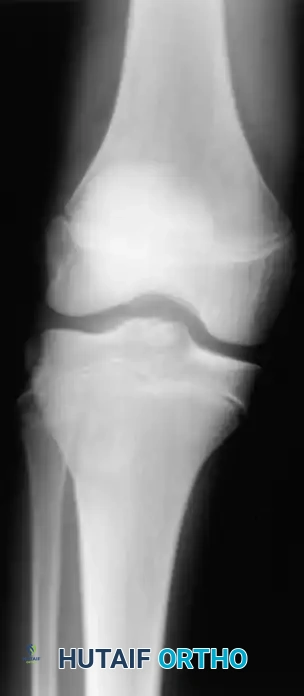

Associated Surgical & Radiographic Imaging

Hutaifortho's Orthopaedic Diagram